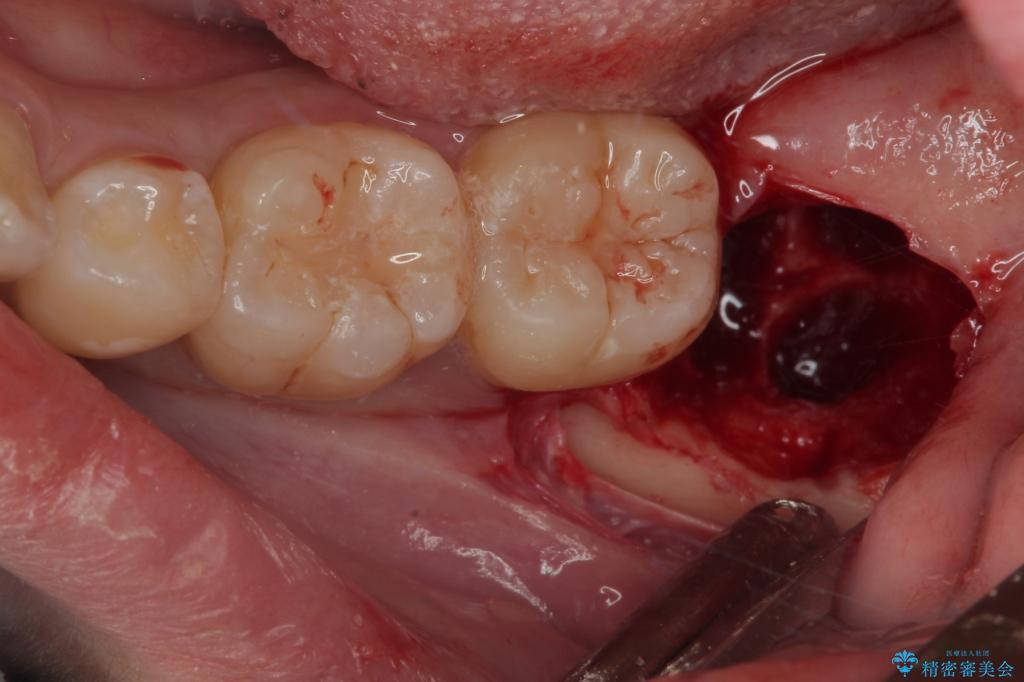

- 親知らずを抜きたいとのことで来院された患者様です。

CTで神経の位置などを確認し、抜歯術を行いました。

しっかり麻酔が効いたことを確認してから安全に抜歯を行いました。